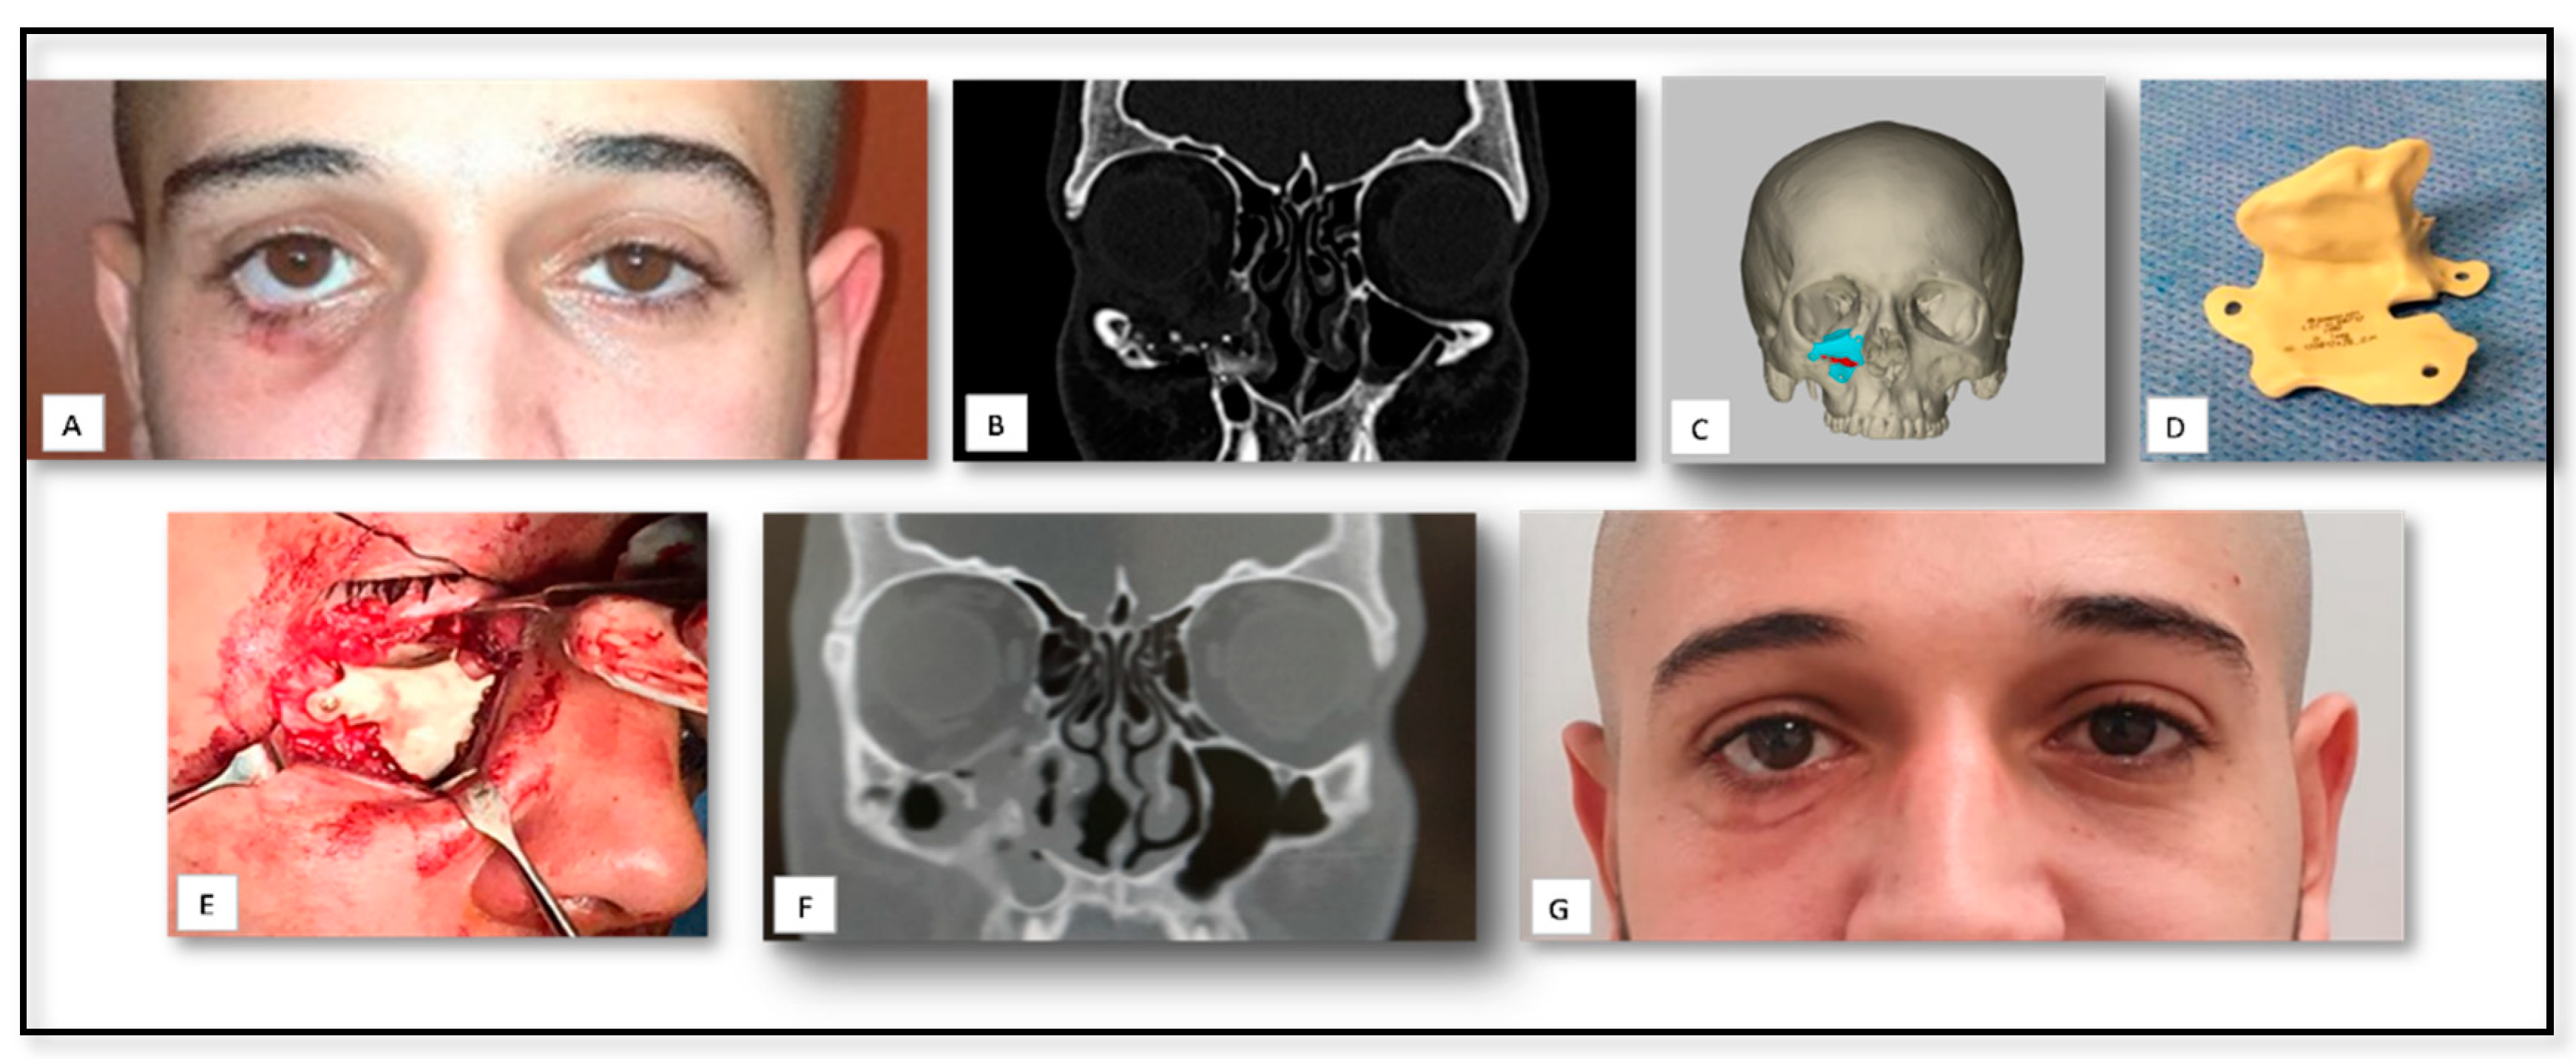

5.3. AM for PSI Manufacturing for Delayed Correction of Post-Traumatic Defects

| 3 | 40 | M | Trauma | Orbit | PSI for floor of orbit reconstruction | Titanium | − | Mild edema |

| 7 | 49 | M | Trauma | Orbit | PSI for floor of orbit reconstruction | Titanium | − | Mild peri-orbital edema |

| 9 | 19 | M | Trauma | Orbit | PSI for floor of orbit reconstruction | PEEK | − | Mild edema |

| 10 | 44 | F | Trauma | Orbit | PSI for floor of orbit reconstruction | Titanium | Loss of accurate fitting | Mild edema |